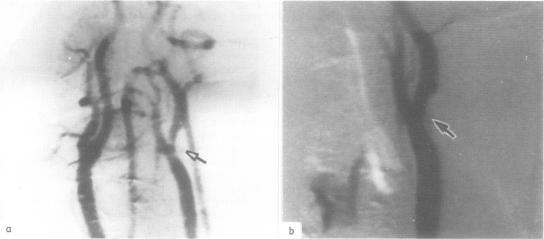

The cervico-cranial arteries were studied using digital subtraction angiography in 50 patients with reversible cerebral ischaemic attacks and normal continuous wave Doppler examination. Digital subtraction angiography was able to visualise the arteries satisfactorily in 45 patients (90%), and revealed minor arterial abnormalities in 12 patients (24%). However, neither occlusions nor stenoses greater than 50% of the diameter of the vessel lumen were found. Although digital subtraction angiography is more accurate than continuous wave Doppler examination in detecting arterial lesions, it did not provide alternative therapeutic choices in any of these patients.

对50例可逆性脑缺血发作且连续波多普勒检查正常的患者,采用数字减影血管造影术对其颈颅动脉进行了研究。数字减影血管造影术在45例患者(90%)中能够令人满意地显示动脉,并在12例患者(24%)中发现了轻微的动脉异常。然而,未发现血管腔直径大于50%的闭塞或狭窄。尽管数字减影血管造影术在检测动脉病变方面比连续波多普勒检查更准确,但在这些患者中均未提供替代治疗选择。